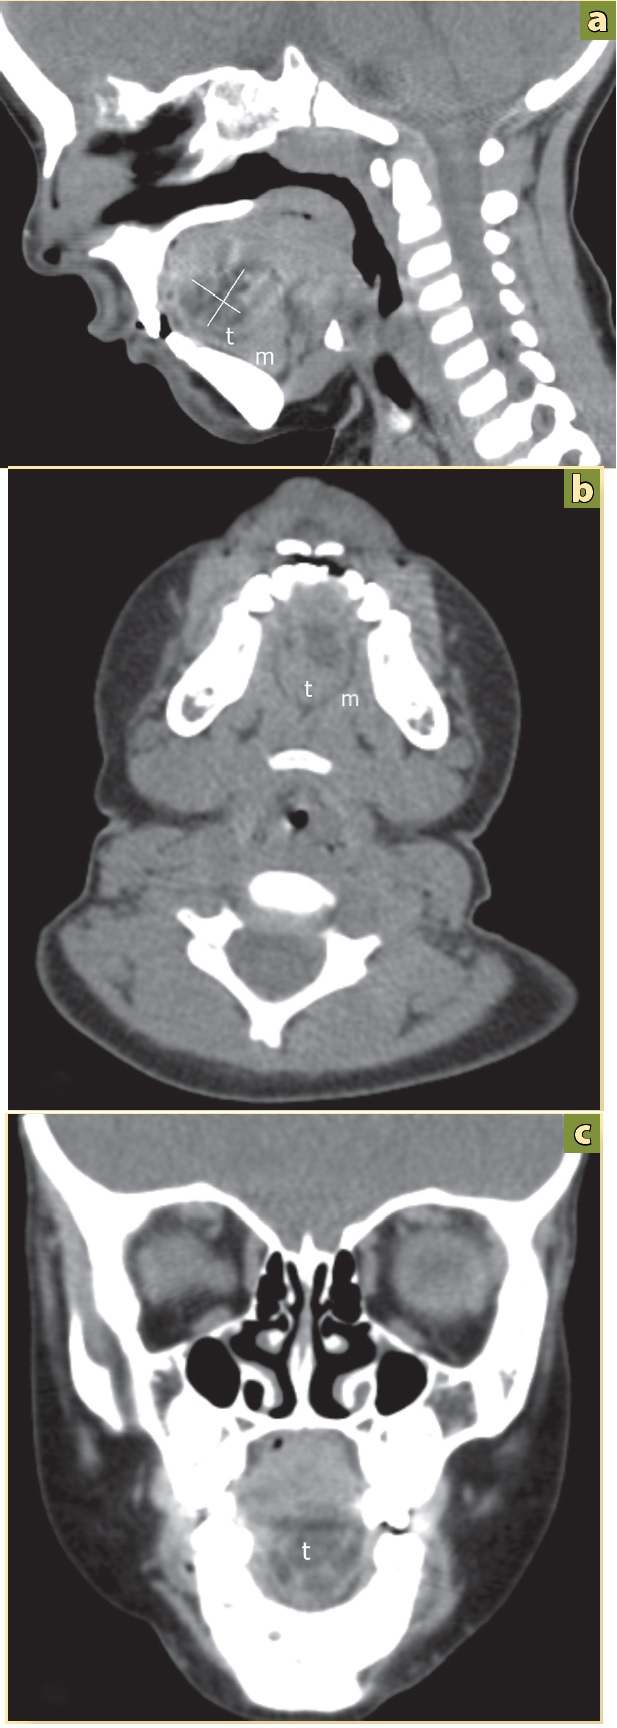

El estudio de tomografia computada (TC) (Figura 3a, 3b, 3c) confirma la lesión encontrada en el ultrasonido.

Figura 3 Tomografía computada: a) Corte axial. b) Corte coronal. c) Corte sagital. Tumor (t) de aspecto quístico en la línea media del piso de la boca, entre el musculo milohiodeo (m), bien delimitada, con mucosa circundante de apariencia normal.